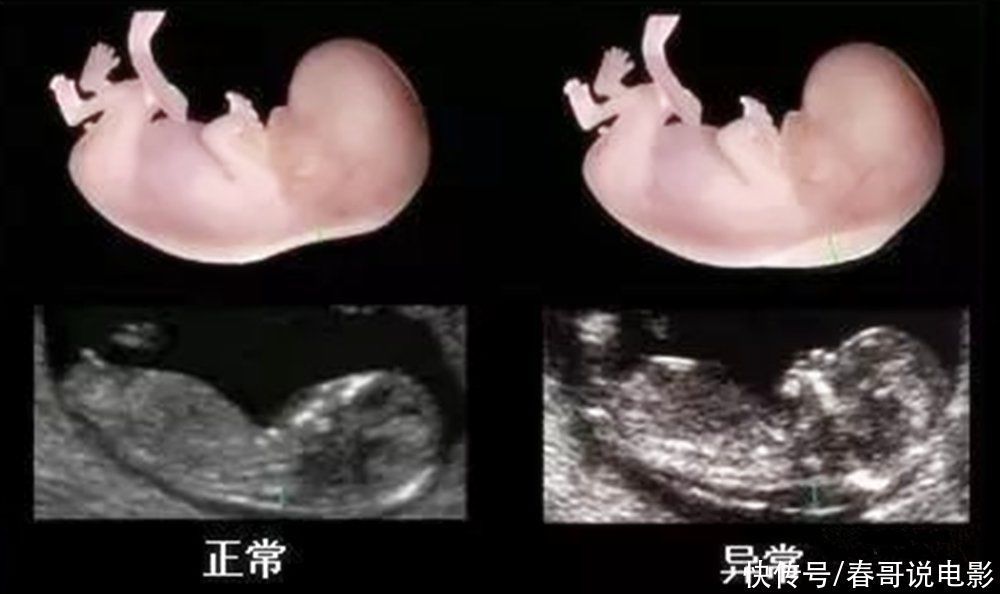

NT检查主要是通过测量胎儿颈部后方透明膜的厚度,来初步判断胎儿是否存在畸形和智力发育方面的欠缺,因此也是不能省略的。

大排畸检查是个孕期所以孕检项目中,检查胎儿部位最全面的一项检查,除了看胎儿的外观,还会检查胎儿内部器官的发育情况。